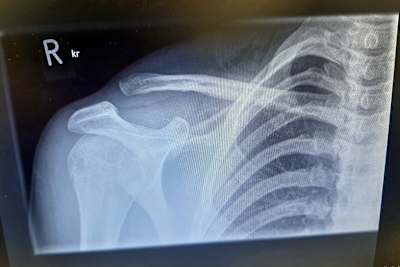

"Wie du weißt", erklärt er gegenüber SPEEDWEEK.com die verzwickten Umstände der Sperre, "hat sich im ersten Freien Training in Schleiz mein Bremshebel verklemmt und hat mich vom Motorrad katapultiert. Bei diesem Sturz riss das Band (Verbindungsgewebe) zwischen Schlüsselbein und Schulter. Ich wusste von früher, dass die IDM-Ärzte sehr konservativ sind und dass sie mich nicht fahren lassen würden." Nach der Röntgen-Aufnahmen im Krankenhaus von Schleiz bestand vor Ort die Möglichkeit, die Verletzung mit einer Metallplatte wieder geradezurücken. Doch nach Rücksprache mit seinem vertrauten Arzt in seiner kroatischen Heimat, fiel die Entscheidung. "Also fuhren wir, mein Vater Ivica, mein Mechaniker David und ich am Freitag von Schleiz nach Zagreb", erzählt Vugrinec vom Trip, der sich mit Hin- und Rückfahrt über 1600 Kilometer zog. "Ich wurde am Samstag um 2 Uhr morgens operiert und schaffte es, kurz vor der Qualifikation in Schleiz zurückzusein." Vom Startplatz 11 fuhr Vugrinec im ersten Renne auf den fünften Platz, im zweiten Lauf schied er bereits in der ersten Runde aus. Beim Rennarzt war er nicht vorstellig geworden. "Du kennst die Ergebnisse, also konnte ich natürlich fahren", lautet seine Ansicht. "Nach meiner Teilnahme an der Weltmeisterschaft in Most war jeder super beeindruckt von meinen Ergebnissen. Aber ich weiß, dass ich eigentlich in die Top-10 der Weltmeisterschaft fahren kann und meine Fans haben es verdient, zu wissen, was passiert ist. Also haben wir es veröffentlicht. Die Reaktionen von allen waren erstaunlich."